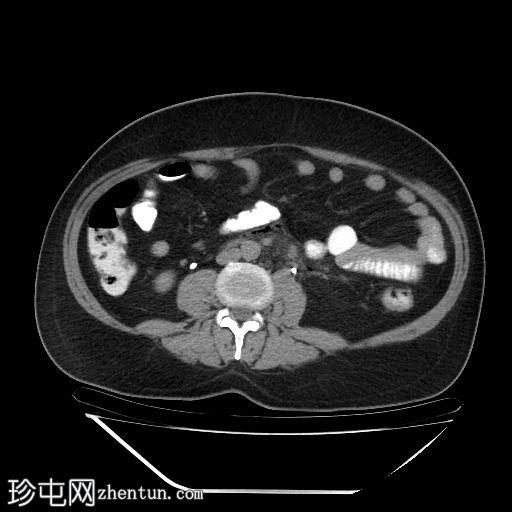

轴位

平扫

降结肠和乙状结肠可见多个小憩室,伴有少量小(亚厘米级)区域淋巴结肿大。周围脂肪和肠壁无明显增厚。

远端降结肠后壁可见一小(<15 mm)、局限性空腔,内含气泡,伴有不规则肠壁强化和轻度邻近肠系膜脂肪条索状改变。

未见脓肿、腹水、弥漫性气腹,提示IA期复杂性急性穿孔性憩室炎(局部穿孔)。